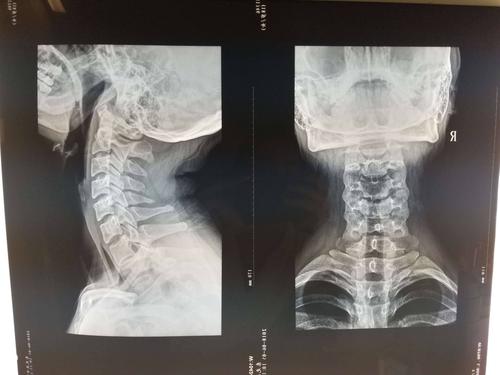

颈椎正侧位

颈椎正侧位,颈椎正侧位报告模板

术前颈椎正侧位片,见颈椎蜕变,局部骨质增生.

颈椎正侧位片

颈椎正侧位x光片

1. 颈椎的生理曲度 正常人的侧位片可见颈椎生理性 前凸.